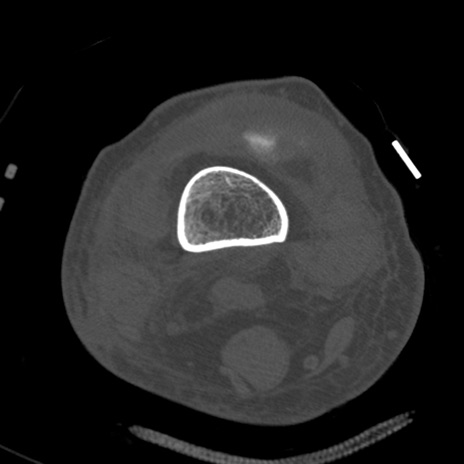

症例28 右膝関節CT(横断像)

右膝関節CT